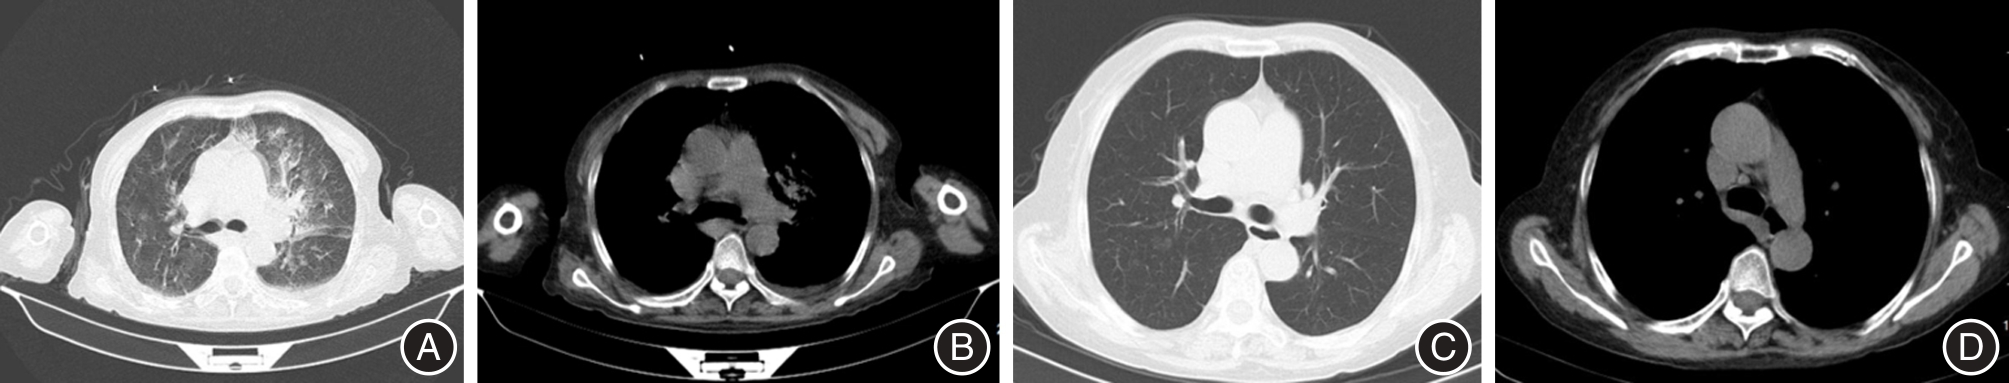

LI Y, HUANG F, CHEN D, et al. Deep Learning Models for CT Segmentation of Invasive Pulmonary Aspergillosis, Mucormycosis, Bacterial Pneumonia and Tuberculosis: A Multicentre Study[J]. Mycoses, 2025, 68(7): e70084-e70084. doi: 10.1111/MYC.70084 .

SHA L, LI W, NA C, et al. Differential clinical and CT imaging features of pneumonic-type primary pulmonary lymphoma and pneumonia: A retrospective multicentre observational study[J]. BMJ open, 2023, 13(10): e077198-e077198. doi: 10.1136/BMJOPEN-2023-077198 .